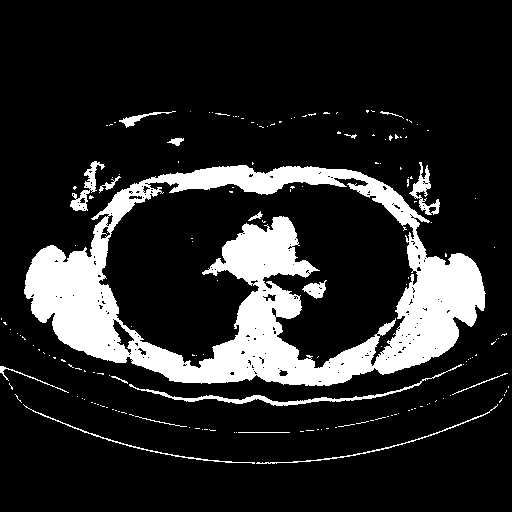

Original VENOUS CT scan

Full window (WL 1023.5, WW 4095 β†’ Low βˆ’1024, High +3071)

Actual HU range: [-1024.0, 3071.0]